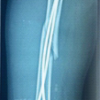

A 35-year-old male, daily wage labor belonging to low socioeconomic status, came with complaints of swelling and pain in his left forearm persisting for the past 5 months following an episode of generalized tonic-clonic seizure. His medical history was suggestive of generalized tonic-clonic seizure for which he was taking combined doses of lamotrigine and valproate as prescribed by his neurologist. Family medical history was significant for parents with similar seizure disorders. The patient had a history of recurrent ulnar fractures having experienced three previous surgeries. In previous instances, the patient underwent operative management with open reduction and internal fixation using a locking compression plate (LCP). He reported that he was working at a construction site where he had an episode of seizure and he fell down. His coworkers took him to the neurologist who intervened promptly and his seizure subsided. He was splinted with a plaster of Paris slab and had follow-up arrangement with the orthopedic surgeon. Instead, the patient’s father had previous surgical treatment with the corresponding author and scheduled follow-up 5 months after the injury. On physical examination, the patient was a 5’10”, 172 lb male with a healthy appearance. The left forearm was noted to have a swelling at the ulnar border of the middle forearm. The skin was intact. The patient had a sharp palpable gap at the mid-forearm region along with local tenderness. There was a notable decrease in pronation and supination compared to the unaffected limb. Neurovascular status was within normal limits. Radiograph of the forearm in anteroposterior and lateral views was performed which revealed a broken LCP with evidence of non-union at fracture site (Fig. 1). Basic blood investigations along with erythrocyte sedimentation rate and C-reactive protein were done. Given the diagnosis of aseptic ulnar diaphyseal non-union with implant failure, the treatment plan involved implant removal and re-fixation of the fracture site. The patient was admitted and after undergoing a thorough pre-operative workup by the anesthetist, he was posted for implant removal and re-fixation with LCP and bone grafting under interscalene block. The patient had a tourniquet applied to the left arm and inflated to 230 mmHg post-exsanguination using an eschmarch bandage during the procedure. We took a standard subcutaneous approach to the ulnar shaft using a straight incision across the non-union site. The plane was made between extensor carpi ulnaris and flexor carpi ulnaris. The implant and fracture site were exposed thoroughly. Implant was removed and the fracture site was assessed for vascularity. To our surprise, 3 cm of non-union site had no vascularity when assessed with drill holes for local signs of bleeding and so this part of ulnar shaft was removed (Fig. 2). We harvested non-vascularized fibula graft from ipsilateral lower limb (Fig. 3), placed it at the fracture site, and passed an elastic nail of 3 mm from olecranon passing through the graft and ulnar shaft (Fig. 4). Finally, a synthes long 10-hole 3.5 mm LCP plate was used and fixed in bridging mode using locking screws across the non-union site (Fig. 5). Four screws were put in proximal shaft, two in the graft site and four in the distal shaft of ulna. The fixation was supplemented with hydroxyapatite granules (G-Bone) (Fig. 6). The patient was kept under observation for 1 day post-surgery and discharged comfortably. The patient received first-generation IV cephalosporin antibiotic for 24 h. Postoperatively, during his stay at the hospital. Postoperatively, arm was protected in an arm pouch and physiotherapy in the form of gentle range of motion exercises was done for 3 weeks. Meanwhile, the patient continued his antiepileptic medications as prescribed by the neurologist. Regular follow-up at 1 month, 3 months, 6 months, and 1 year post-surgery was done. X-ray at final follow-up after 1 year revealed complete union at the fracture site (Fig. 7) with an acceptable range of motion as compared to the unaffected limb (Fig. 8).